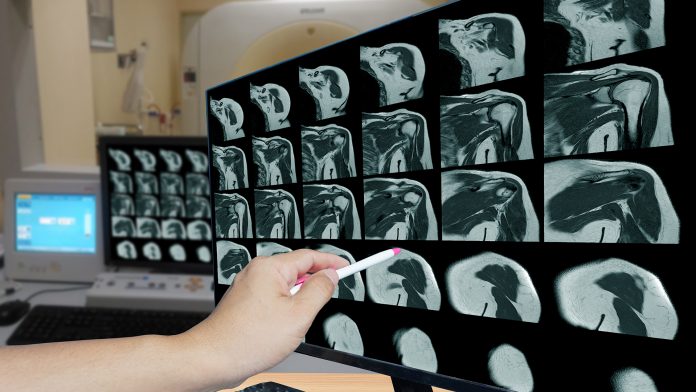

Boston University researchers have argued that AI can help with image interpretation and decrease reporting time in musculoskeletal radiology.

In a new study, Boston University researchers have outlined the role that AI applications can have within musculoskeletal radiology. This includes helping with image acquisition and interpretation and prediction of future outcomes.

As musculoskeletal imaging volumes continue to rise, there is a lack of sub-specialised musculoskeletal radiologists to interpret results. AI tools have the potential to help musculoskeletal radiologists with their workload, which is ever-increasing.

“With the ongoing trend of increased imaging rates and decreased acquisition times, a variety of AI tools can support musculoskeletal radiologists by providing more optimised and efficient workflows,” said corresponding author Ali Guermazi, MD, PhD, chief of radiology at VA Boston Healthcare System and professor of radiology and medicine at Boston University Chobanian & Avedisian School of Medicine.